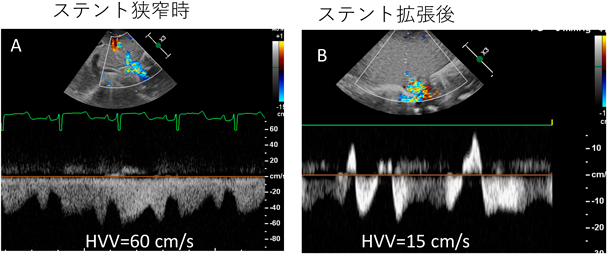

総肺静脈還流異常症(下心臓)に対する静脈管ステント留置後の新たな再狭窄評価法Novel Method to Evaluate Restenosis after Ductus Venosus Stenting for Infracardiac Type Total Anomalous Pulmonary Venous Return